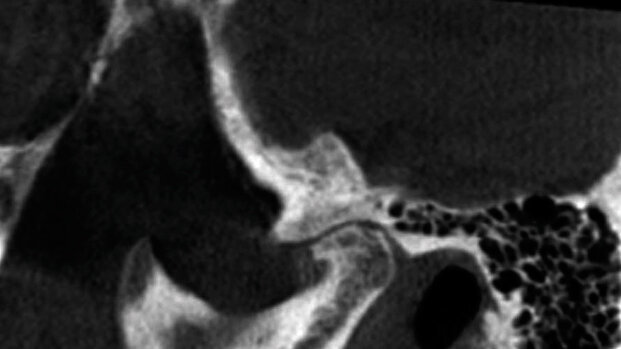

Solo negli ultimi 15 anni la Cone Beam Computed Tomography (CBCT) è stata utilizzata per l’imaging e l’analisi dell’ATM. Prima di questo, una delle principali modalità di valutazione dell’ATM era la Multidector Computed Tomography (MDCT). Gli studi hanno tuttavia dimostrato che la CBCT è paragonabile per la sua precisione alla MDCT quando si mettono a confronto le distanze degli spazi comuni e i dettagli della superficie corticale. Una delle indicazioni principali della CBCT riguardo alla diagnostica ATM è quella di chiarire i cambiamenti ossei nei pazienti con osteoartrite (OA). La CBCT è stata risolutiva per definire con precisione i cambiamenti della superficie ossea, così come i cambiamenti erosivi sulla testa del condilo osservati nell’artrite reumatoide (AR). Possiamo ottenere accurate immagini delle superfici articolari per valutare gli osteofiti (proiezioni ossee angolari) e un normale aspetto arrotondato della superficie condilare, con o senza la presenza di erosione. Altre indicazioni della CBCT per l’ATM sono le fratture intra-articolari e l’anchilosi osteofibrosa. Uno studio ha dimostrato che viene cambiata la decisione clinica se presa sulla base della CBCT, mentre in precedenza era basata sulla valutazione fisica e panoramica. La CBCT è una conveniente alternativa alla TC per la valutazione dell’ATM, sebbene sia più sensibile agli artefatti. La valutazione diagnostica dell’ATM con la CBCT è limitata ai componenti articolari e all’integrità della corticale ossea.